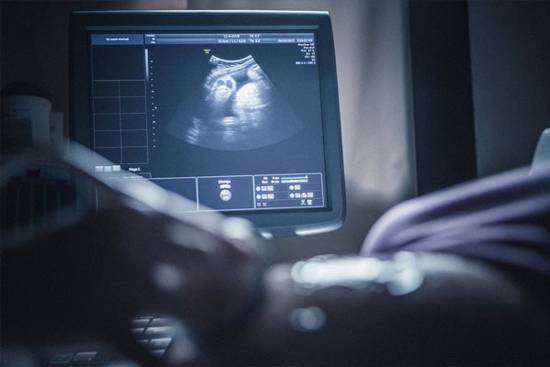

نایب رئیس کمیسیون مشترک طرح حمایت از خانواده و جوانی جمعیت مطرح کرد: با تشکیل کمیته غربالگری در کمیسیون و همفکری با متخصصان مقرر شد غربالگری حذف نشود بلکه اختیاری، علمی و با نظر پزشک متخصص انجام شود.

محمدبیگی اظهار کرد: در کمیسیون مشترک طرح حمایت از خانواده و جوانی جمعیت، کمیته غربالگری تشکیل شد و متخصصان زنان در این جلسات حضور یافتند و نتیجه بررسیها این شد که غربالگری حذف نشود بلکه اختیاری، علمی و با نظر پزشک متخصص مورد توجه قرار گیرد.